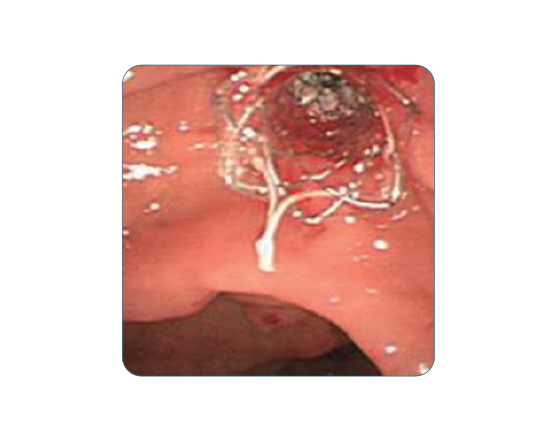

Bumpy yapısı sayesinde migrasyon riskini en aza indirir. Safra yolu darlıklarında etkili bir çözümdür.Kaplı yapısı doku içi büyümeyi engeller. Uzun vadeli kullanım için uygundur.